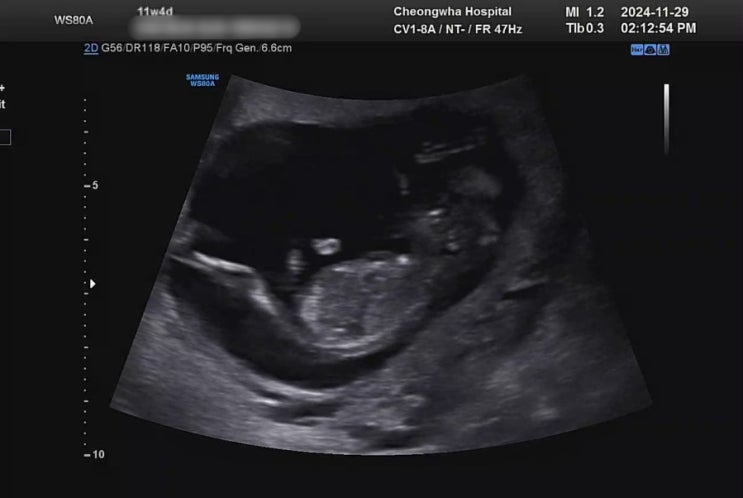

[임신기록] 10주차 ~ 13주차 일상 / 산후조리원 계약 / 산전검사 / 1차기형아 검사

분만병원 결정완료.. 강남차와 청화병원 두 개를 끝까지 고민하다가 강남차병원 조리원이 언제 다시 오픈할...